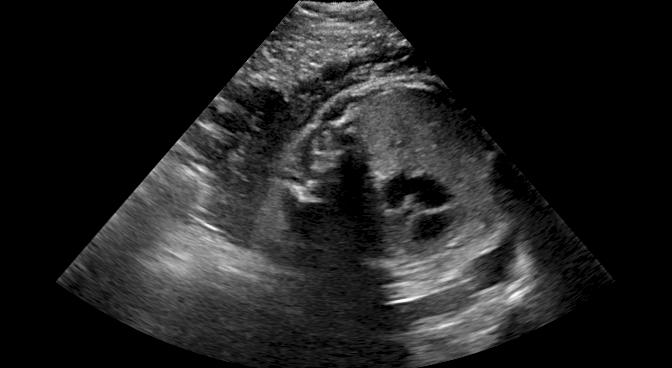

Fig. 9 qualitatively shows that shadow confidence maps are able to improve the performance of US image fusion algorithms with different weighting strategies. Fig. 9 also shows the difference between adding two different types of confidence maps. These two types of confidence maps are generated by the confidence estimation network which are separately trained by either MSE or Sigmoid loss. Fig. 9 (a) to (d) illustrate image fusion results for the same case using different combinations of weighting strategies and loss functions. The difference maps indicate that shadow confidence maps are capable of improving image fusion performance. Fig. 9 (e) to (h) show image fusion results on four different cases. We randomly select two positively affected cases (Fig. 9 (e) and (f)) to show visual improvement. We additionally show two randomly selected examples (Fig. 9 (g) and (h)) that don’t show perceptually significant improvements after adding shadow confidence maps. Quantitative evaluation for image fusion is not possible because of lacking a ground truth for US compounding tasks.

-G Examples for Image Fusion

Fig.15 shows more examples of the multi-view image fusion task which include the original multi-view images. From the column (a-b) of Fig.15, we can see that the original images contain strong shadow artifacts that can affect the anatomical analysis. The image fusion task aims to use complementary information from images with different views for reducing artifacts and increasing anatomical information. Column (e-f) enlarge the areas within the bounding boxes in column (c-d). Column (g) shows the difference masks between column (e)and (f). The difference masks clearly indicates the improved performance of image fusion after adding shadow confidence maps for Gaussian weighting strategy as well as Intensity and Gaussian weighting strategy.